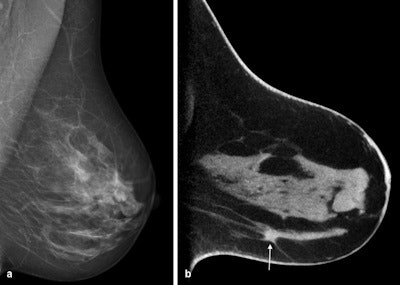

At DRK 2016, she is reporting on a further development in tomosynthesis: cone-beam breast CT. Unlike tomosynthesis, this method actually allows for a 3D dataset to be acquired.

Cone-beam breast CT has some advantages that may render the method an interesting option for breast cancer screening in the future. On the one hand, thanks to 3D image acquisition, the location of suspicious structures can be determined precisely in all spatial directions. On the other hand, findings can be evaluated immediately by taking a tissue sample, thus sparing the affected women days of uncertainty. Compared with mammography, the method is also more comfortable for the women because the breast does not need to be compressed during the examination.

For her pilot study, Wienbeck examined more than 100 female patients by means of cone-beam breast CT, including both women with malignant cancer as well as those with benign findings.

"The most important outcome is that this new method allows us to detect a very high percentage of malignant tumors," she stated.

However, even this method is somewhat dependent on the density of the breast: The detection rates are lower with dense breast tissue. In this case, the detection rate can be improved by administering a contrast agent. To evaluate how cone-beam CT fares against mammography, the researchers are now embarking on a larger clinical study, during which the team from Göttingen will collaborate with their peers in Norway and Berlin.